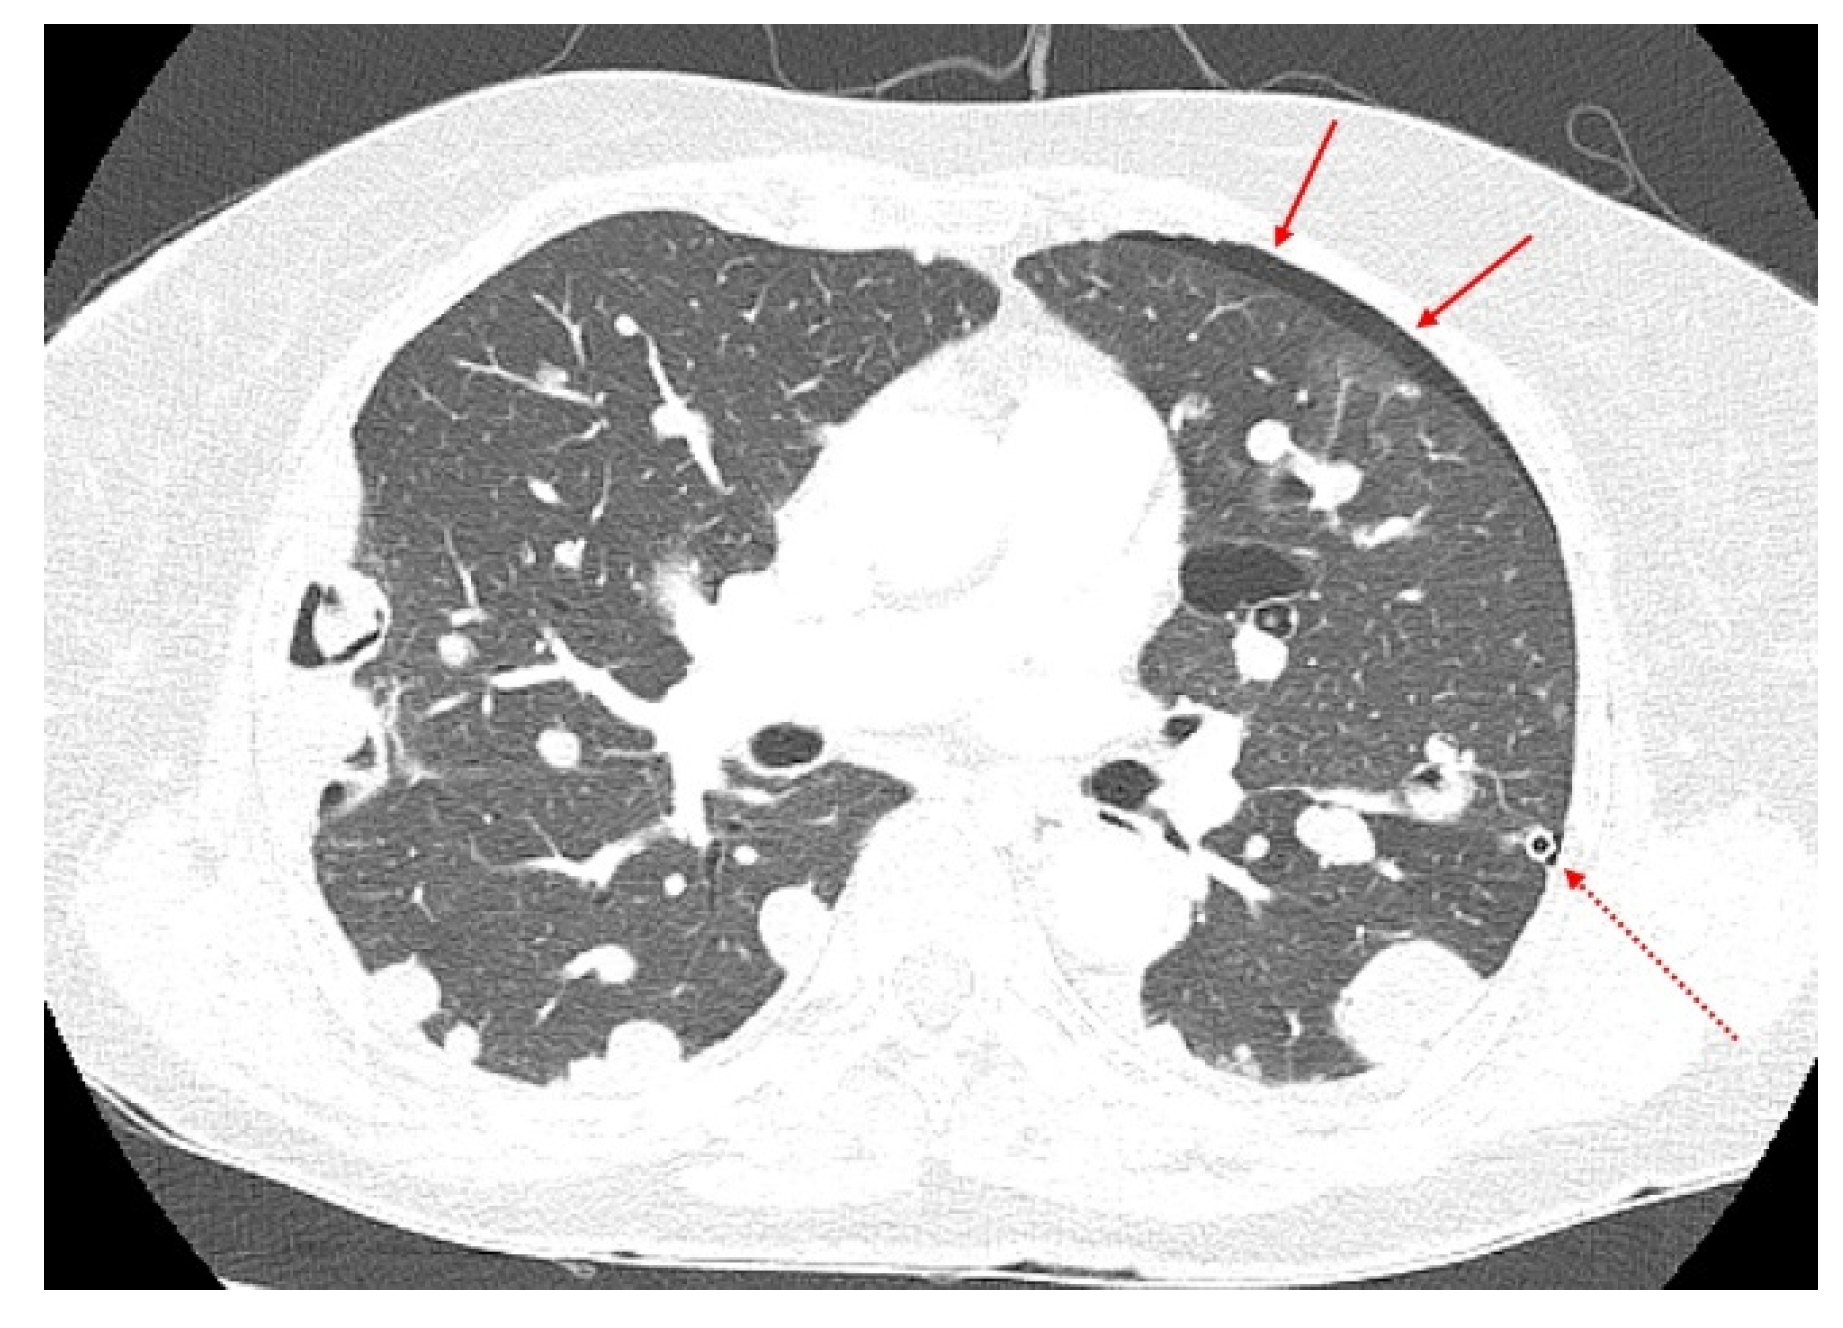

A 70-year-old woman visited the clinic complaining of acute cough and dyspnea in April 2017. A chest X-ray and chest computed tomography (CT) revealed pneumothorax in the left chest and multiple nodules in both the lungs (Figure 1).

Figure 1.

A chest computed tomography (CT) features of the lung masses. A chest CT (April 2017) showed pneumothorax in the left lung and multiple masses in both lungs. The amount of pneumothorax was small (solid arrows) because CT was performed after the chest tube (dotted arrows) was inserted and stabilized.